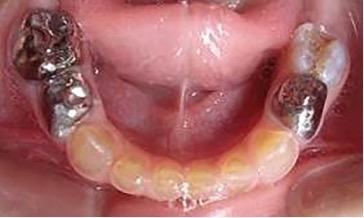

El examen clínico intraoral reveló alteración de la estructura y color de las piezas primarias, atrición y pérdida de la dimensión vertical (Figura 2). Radiográficamente se observó la presencia de coronas con marcada constricción cervical y raíces cortas (Figura 3). Presentaba alto riesgo cariogénico, por la presencia de lesiones de caries activas y dos restos radiculares, sumado a la anomalía estructural de la dentina (riesgo biológico específico) y bajo riesgo gingivoperiodontal. El riesgo socio-económico era alto por provenir de una familia con marcadas limitaciones económicas. Luego de la anamnesis, examen clínico y radiográfico, e interconsulta con el médico de cabecera se estableció el diagnóstico de DI Tipo I asociado a OI tipo I. Se planificó un tratamiento integral y preventivo con los objetivos de devolver forma y función, y proteger y evitar el desgaste de los tejidos conductas que pudieran interferir con el tratamiento.

Figura 2: Examen clínico intraoral del maxilar superior e inferior y vista anterior. Año 2007